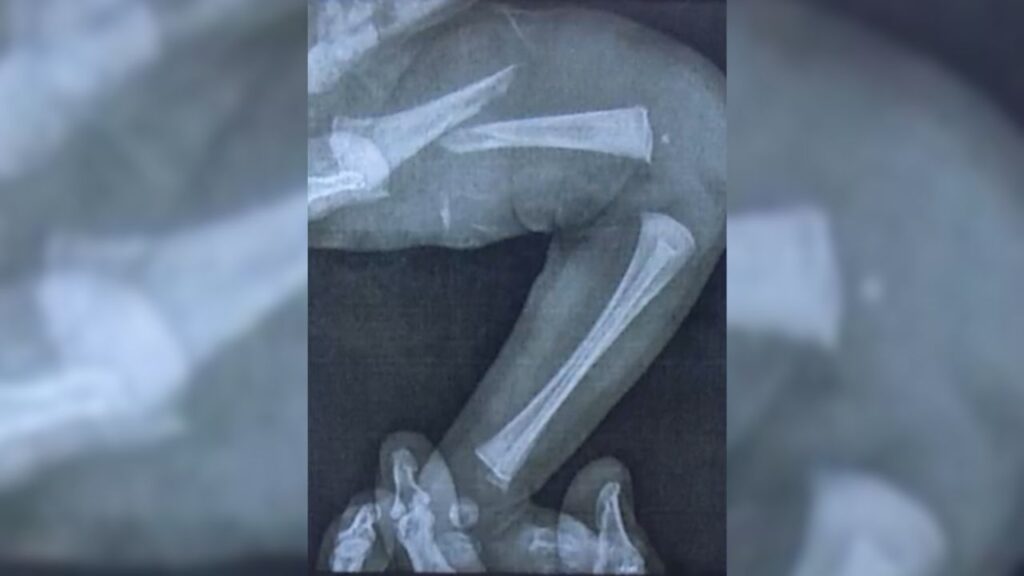

Em casa, a situação piorou. A bebê continuava chorando sem parar e desenvolveu inchaço e hematomas na perna esquerda. Depois de buscar atendimento em três unidades de saúde, um exame de raio-x finalmente revelou a gravidade: o fêmur da recém-nascida estava fraturado.